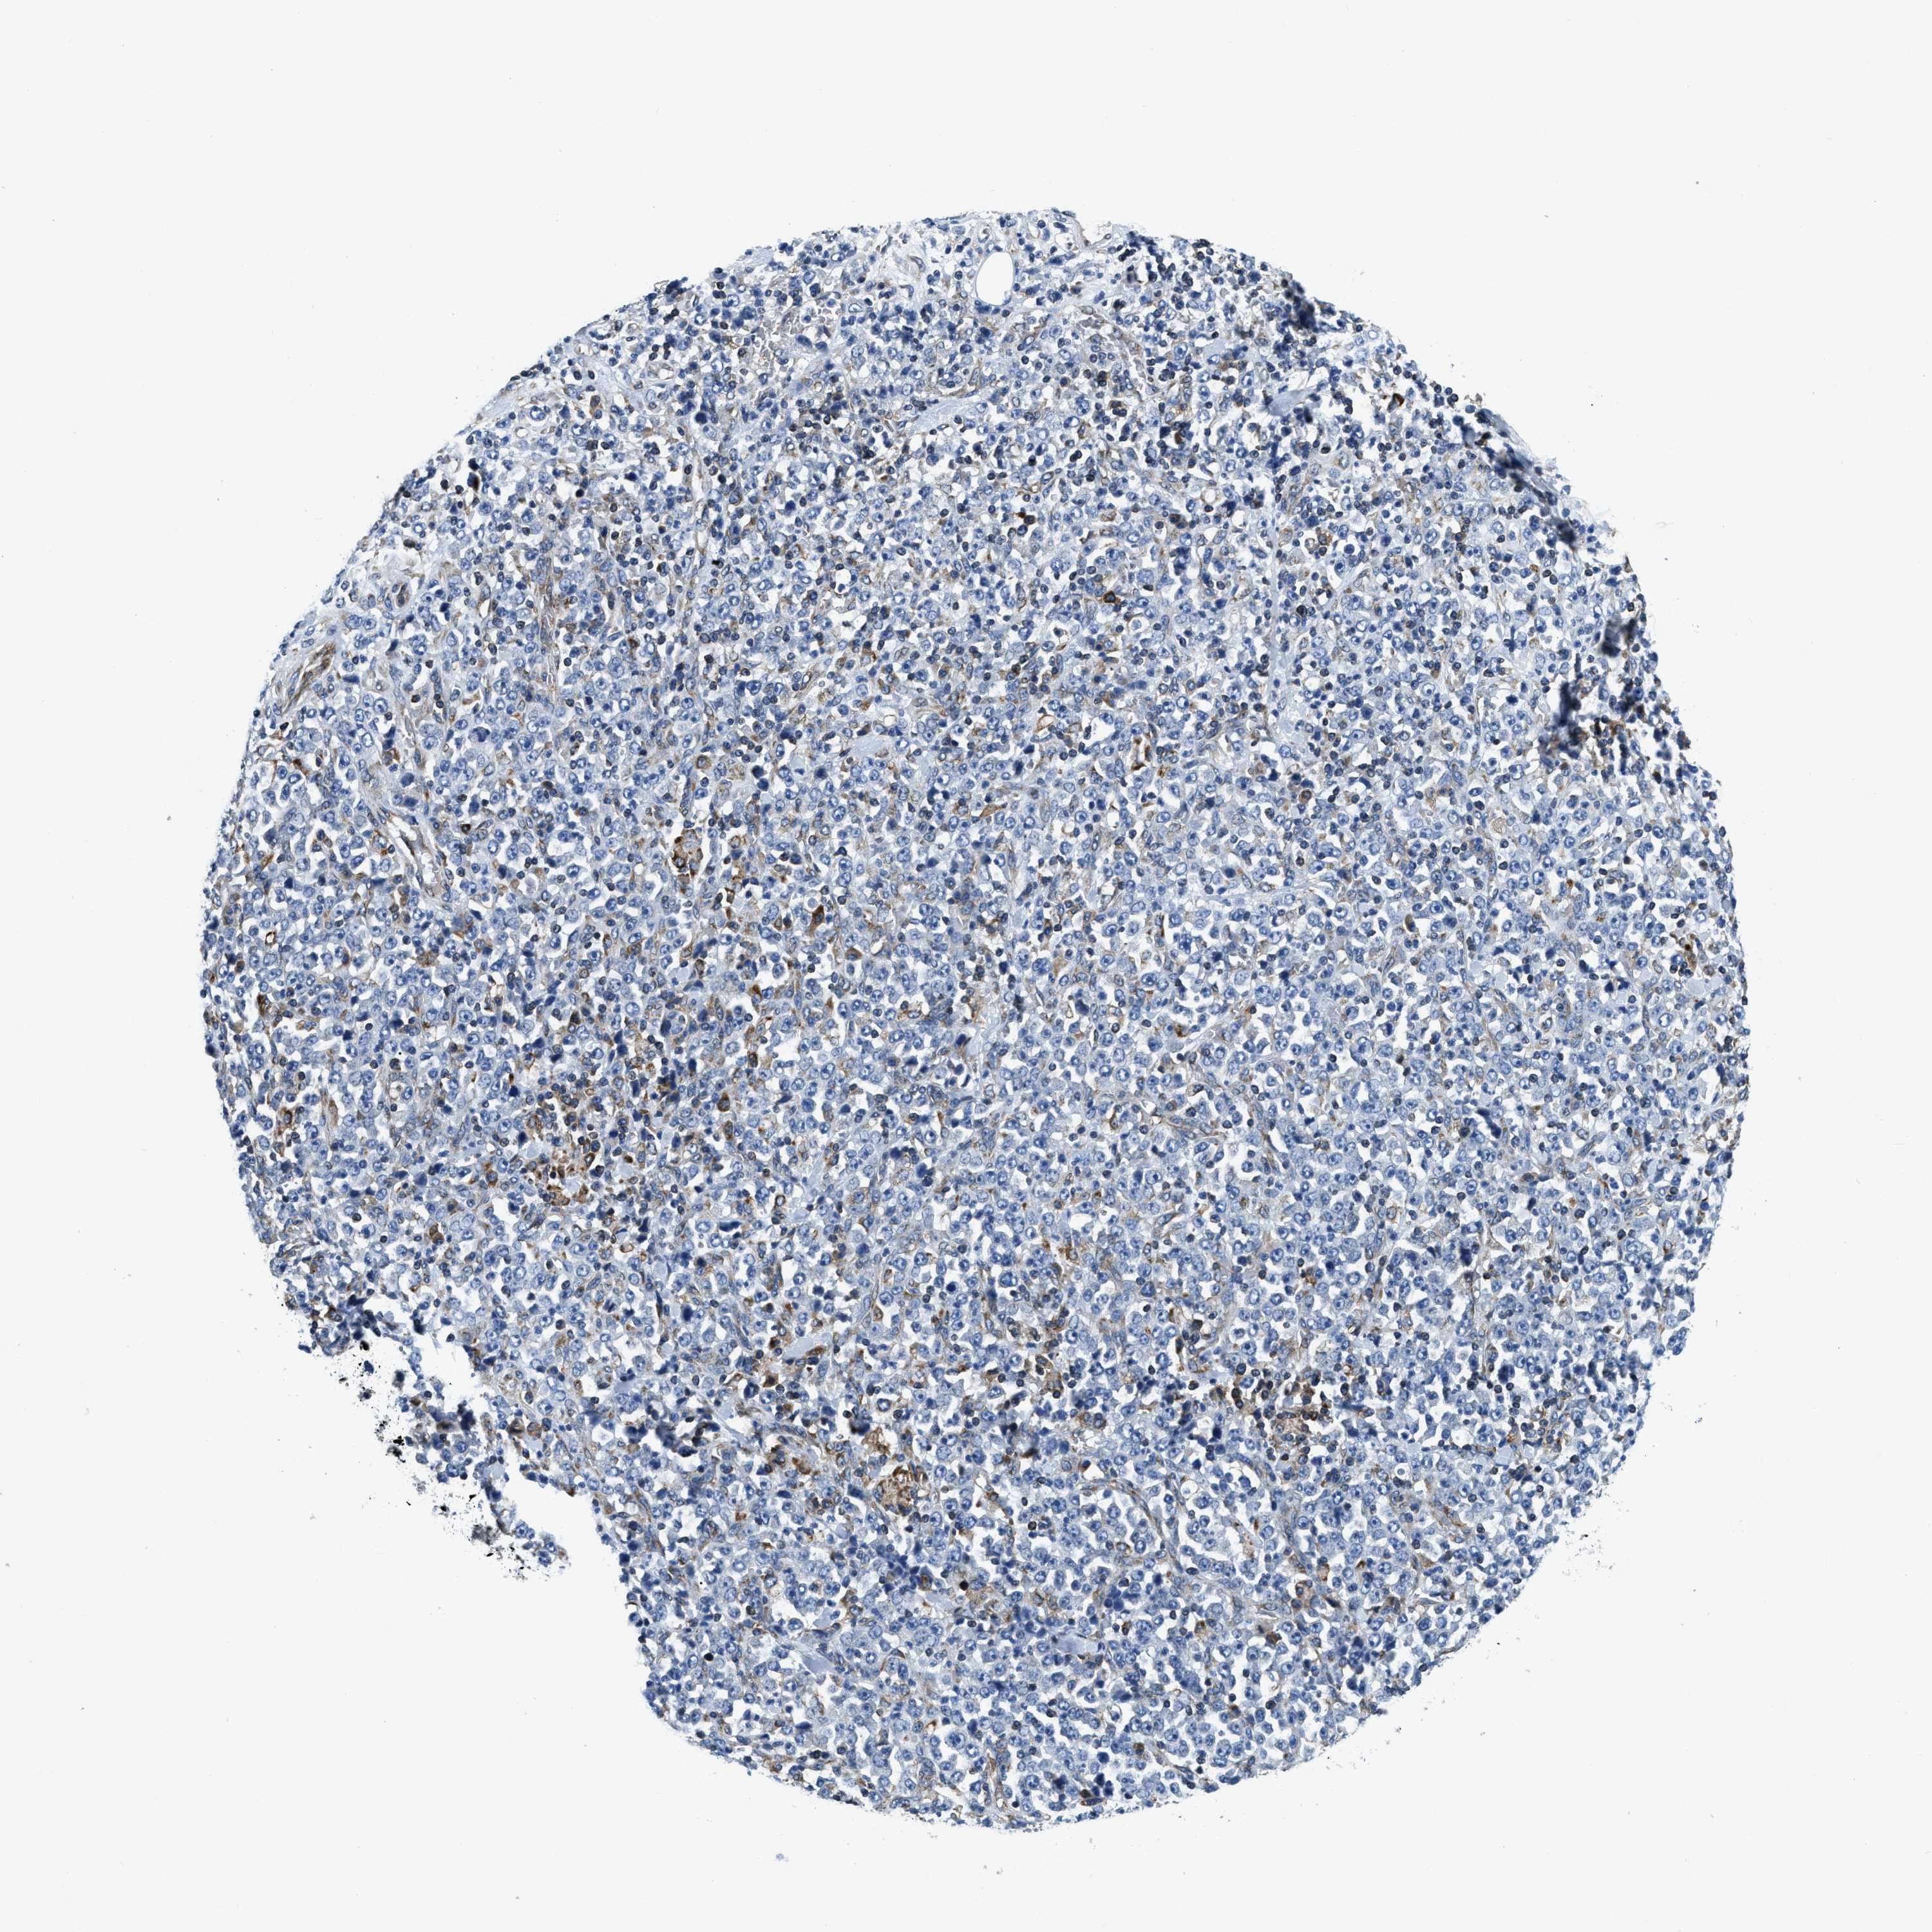

STOMACH CANCER - Protein expressioni

A mouse-over function shows sample information and annotation data. Click on an image to view it in a full screen mode. Samples can be filtered based on level of antibody staining by selecting one or several of the following categories: high, medium, low and not detected. The assay and annotation is described here.

Antibody stainingi

Antibody staining in the annotated cell types in the current human tissue is reported as not detected, low, medium, or high, based on conventional immunohistochemistry profiling in selected tissues. This score is based on the combination of the staining intensity and fraction of stained cells.

Each image is clickable and will lead to virtual microscopy that enables deeper exploration of all samples and also displays staining intensity scores, fraction scores and subcellular localization as well as patient and tissue information for each sample.

Antibody HPA019698

Staining

High

Medium

Low

Not detected

Intensity

Strong

Moderate

Weak

Negative

Quantity

>75%

75%-25%

<25%

None

Location

Nuclear

Cytoplasmic/membranous

Cytoplasmic/membranous,nuclear

Adenocarcinoma, NOS